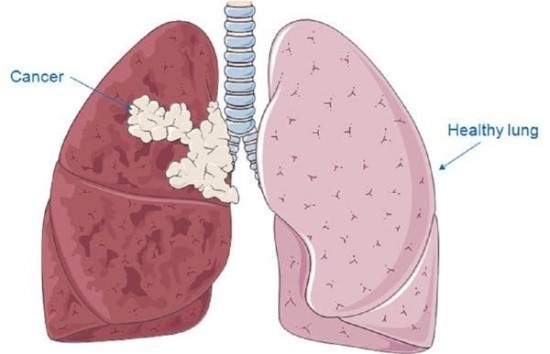

폐암은 위암, 갑상선암 다음으로 3번째로 발병 빈도가 높은 3대 암 중 한 가지입니다. 폐암은 재발과 전이까지의 빈도도 잦은지라 완치가 어렵다고 하며 폐암 발병 초기에는 거의 증상이 없을 수가 있어 수술이 불가능한 3기, 혹은 4기에 주로 진단된다고 합니다.

폐암 4기에 이르게 되면 5년 생존률이 30% 대로 떨어지게 된다고 합니다. 그리해서 폐암은 암 질병이자 중 사망자 비율이 가장 높은 것으로 나타나고 있습니다.

폐암은 사망률 2위를 차지하고 있는 간암에 비해 무려 2배에 가까운 사망률을 보이고 있다고 해요. 이렇게 치명적인 폐암에 대해 미리 알고 대처하는 것이 바람직할 것 같습니다. 아래에서는 폐암이라 판단해 볼 수 있는 그 초기증상에 대해 간단히 설명드리겠습니다.